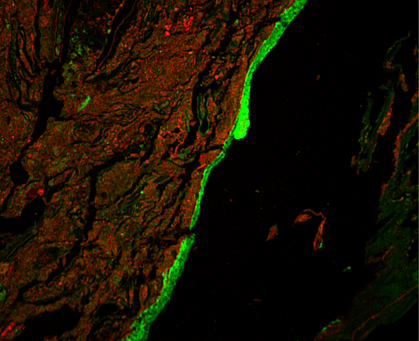

A research team led by Dr. Lijun Xia from the Oklahoma Medical Research Foundation developed an imaging method to visualize mucus production in the entire colons of mice. They examined O-glycosylated mucus production and its effects on gut bacteria in healthy mice and those with a disrupted microbiome.

The imaging showed that, contrary to current thinking, most gut mucus production happened in the proximal colon (the first and middle parts). Clumps of fecal matter and bacteria were coated with this mucus as they traveled through the colon. They then picked up a different type of mucus produced in the distal colon (the last part, closer to the rectum). Together, the two types of mucus encased the fecal pellets and largely kept bacteria from directly interacting with the tissue lining the colon.

When the team disrupted mucus O-glycosylation, this protective gut barrier broke down. Mice engineered to lack the sugar molecules necessary to make mucus in one or both parts of the colon could not encapsulate fecal pellets as effectively. These mice also had microbes living substantially closer to their gut tissue than mice with healthy mucus production. The O-glycosylated mucus affected the makeup and metabolic function of the encapsulated microbes as well.

Correspondingly, mice lacking these sugar molecules in the proximal colon were more vulnerable to developing inflammation and injury in the distal colon.